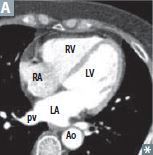

What is the most posterior part of the heart? The most posterior part of the heart is the left atrium.

What is the most posterior part of the heart? The most posterior part of the heart is the left atrium